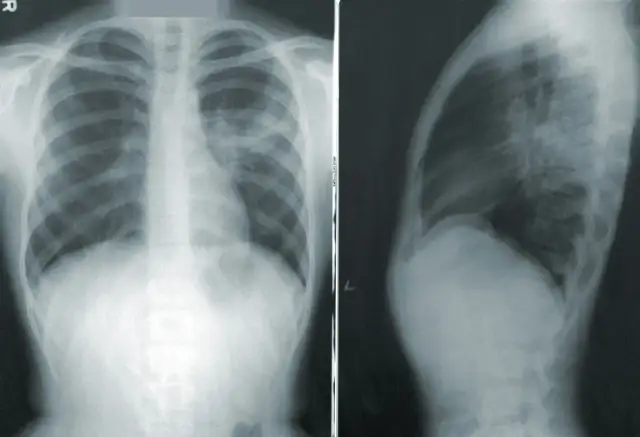

Badania dodatkowe: Kiedy konieczne jest RTG klatki piersiowej lub badanie krwi?

W niektórych sytuacjach, aby postawić trafną diagnozę, lekarz może zlecić dodatkowe badania. Na przykład, przy podejrzeniu zapalenia płuc, zwłaszcza jeśli osłuchowo słychać zmiany lub dziecko ma uporczywą gorączkę i duszności, konieczne może być wykonanie RTG klatki piersiowej. Badanie krwi, w tym morfologia z rozmazem i parametry stanu zapalnego (np. CRP), może pomóc w ocenie, czy mamy do czynienia z infekcją wirusową, czy też doszło do nadkażenia bakteryjnego. Czasami, w przypadku nawracających problemów z uchem, lekarz może skierować na konsultację laryngologiczną.